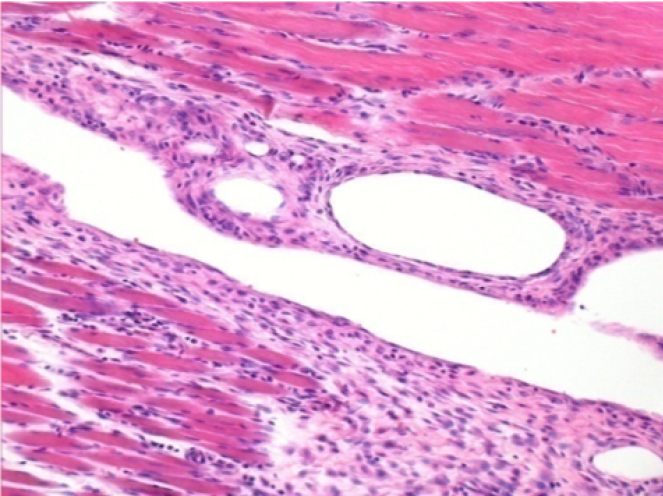

0.5 ml ( 5x 0.1ml) Endopeel SC Injection in the right subcutaneous pretibial area.

R-D10-SC-200X